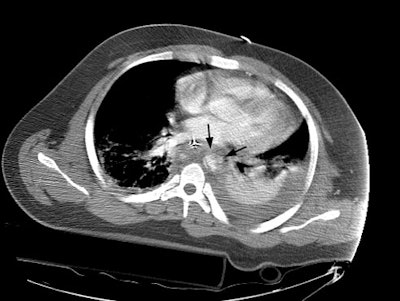

A CT scan of the chest demonstrated a large mediastinal hematoma (yellow arrows) and a left pleural fluid collection that was subsequently found to be a hemothorax. There was irregularity to the aortic arch near the isthmus (black arrow) which is highly suspicious for an aortic laceration, however, images at the level of the diaphragmatic hiatus demonstrated a more impressive finding (below).

CT images more inferiorly revealed an intimal flap and marked irregularity to the contour of the aorta consistent with traumatic injury (black arrows). Slightly below this level there was a near complete lack of opacification of the vessel (lower image).